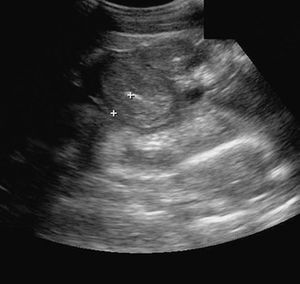

診断

●臨床徴候

●身体診察

●臨床検査